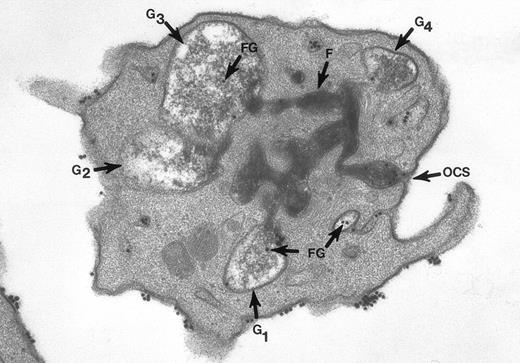

Thin section of a platelet from a sample of washed cells incubated with Fgn/Au particles for 15 minutes, then exposed to 5 U/mL of thrombin for 60 seconds before fixation in glutaraldehyde-tannic acid-osmium to selectively stain the platelet glycocalyx, fibrinogen, and fibrin. This example is one of several serial sections through the same platelet. It and the other serial sections show the typical features of shape change and internal transformation caused by thrombin. Fgn/Au particles are bound to the irregular surface and are in the process of entering channels of the OCS. The OCS channel indicated by an arrow (↑) is filled with fibrinogen and fibrin stained by tannic acid-osmium black. The tortuous channel is connected directly to several granules (G1, G2, G3) in various stages of labelization. Residual fibrinogen is stained by the reaction product. Fgn/Au particles carried by the OCS have entered the granules (G1, G3, G4). The direct connections between OCS channels and granules in this example and its serial sections is indisputable. Original magnification ×45,000. (Reprinted with permission.19)

The surface and OCS membranes are the only structures stained by osmium black in resting platelets. After exposure to thrombin, the dense stain also enters α granules that have become labelized and communicate with the OCS.20 Fibrinogen and fibrin in the process of extrusion from α granules fill channels of the OCS. During this process the OCS becomes dilated, as do the labelized α granules, yielding the appearance of swollen vacuoles (Fig 2). In experiments where the platelets were combined with fibrinogen-coated gold particles before exposure to thrombin and fixation through the tannic acid staining procedure, Fgn/Au was present in OCS channels and in swollen α granules. The findings showed that the OCS is a two-way street, and α granules communicate with channels of the OCS to secrete their contents.